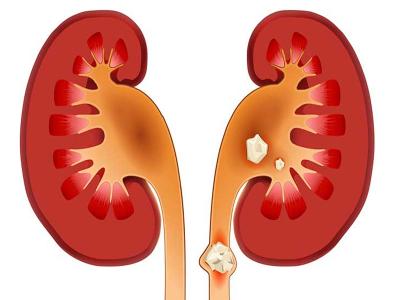

किडनी की पथरी खनिज और लवणों से बने कठोर पदार्थ होते हैं। किडनी की पथरी के कई कारण होते हैं और आपके मूत्र मार्ग के किसी भी हिस्से को प्रभावित कर सकते हैं। अक्सर पथरी का निर्माण तब होता है, जब पेशाब गाढ़ा हो जाता है, जिससे खनिज क्रिस्टलीय हो जाते हैं और एक साथ चिपक जाते हैं। गुर्दे की पथरी होने पर काफी दर्दनाक हो सकता है। लेकिन आमतौर पर पथरी से कोई स्थायी नुकसान नहीं होता है। आपकी स्थिति के आधार पर, आपको गुर्दे की पथरी को पारित करने के लिए दर्द की दवा लेने और बहुत सारा पानी पीने के अलावा और कुछ नहीं चाहिए।

एक गुर्दे की पथरी होने पर आपको पसलियों के नीचे, पक्ष और पीठ में गंभीर दर्द होना, यह दर्द पेट और कमर के निचले हिस्से में होता है। दर्द जो लहरों में आता है और तीव्रता में उतार-चढ़ाव होता है। पेशाब करने पर दर्द होना, गुलाबी, लाल या भूरे रंग का मूत्र, बदबूदार या दुर्गंधयुक्त पेशाब, मतली और उल्टी, लगातार पेशाब करने की जरूरत होना, सामान्य से अधिक बार पेशाब करना, यदि कोई संक्रमण मौजूद है तो बुखार और ठंड लगना और छोटी मात्रा में पेशाब करना आदि शामिल हैं।